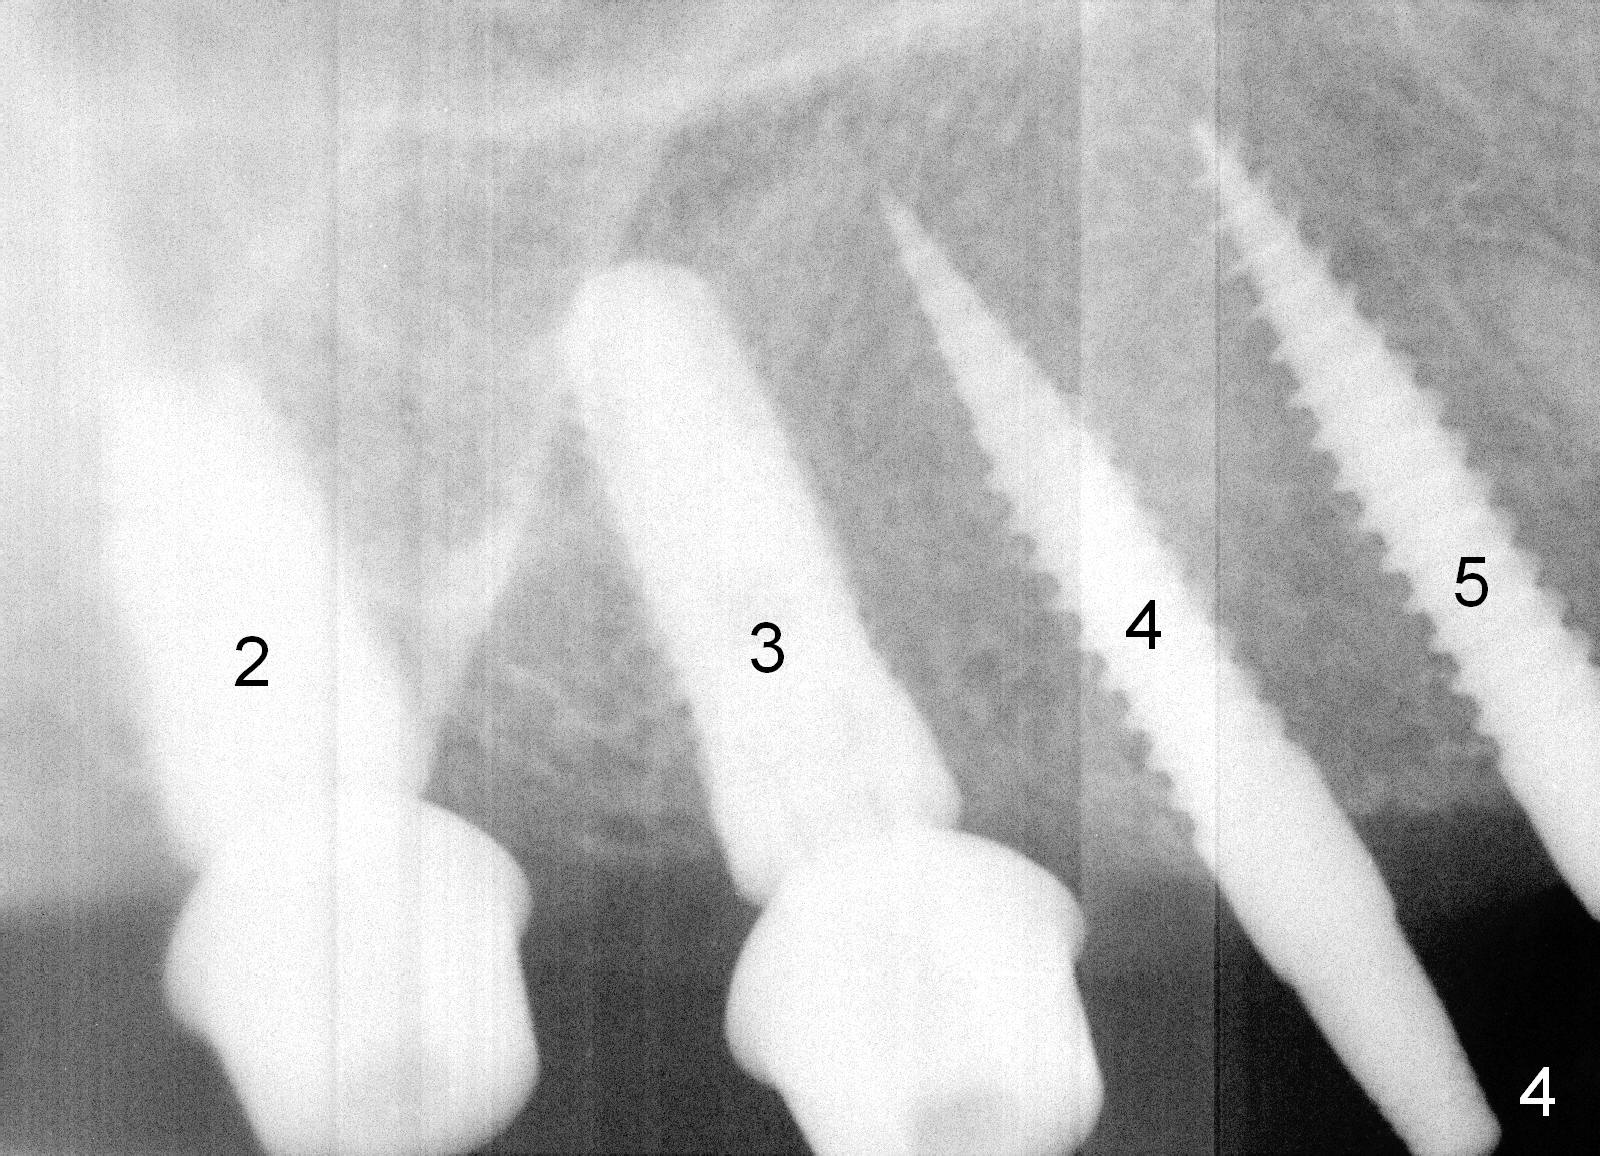

Osteotomy in the upper posteriors starts through a surgical stent for 12 mm.  After incision, each osteotomy is examined, adjusted and extended 2 mm shy of intended (Fig.1,2).  It appears that the trajectories at #4,5 are off (Fig.2).  After re-adjustment, the trajectories are acceptable (Fig.3 (red dashed line; part of the root of the tooth #6)).  Four implants are placed basically in accordance with the plan: 5.9x10 mm at #2, 5x14 at 3, and 3x14 mm 1-piece at 4 and 5 (Fig.4,5).  Fig.6 shows the narrow ridge at #4 and 5 after implant placement.  Although abutments are placed at #2 and 3, an immediate provisional bridge cannot be fabricated because of lack of enough clearance (supraeruption of the opposing dentition).